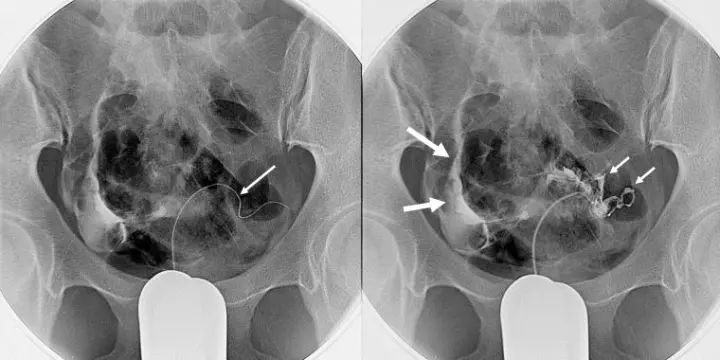

在DSA机下,隔着肚皮看到肝内癌灶是很轻易的事

输卵管不通引起不孕,介入入路是经阴道子宫的自然途径,没有创口